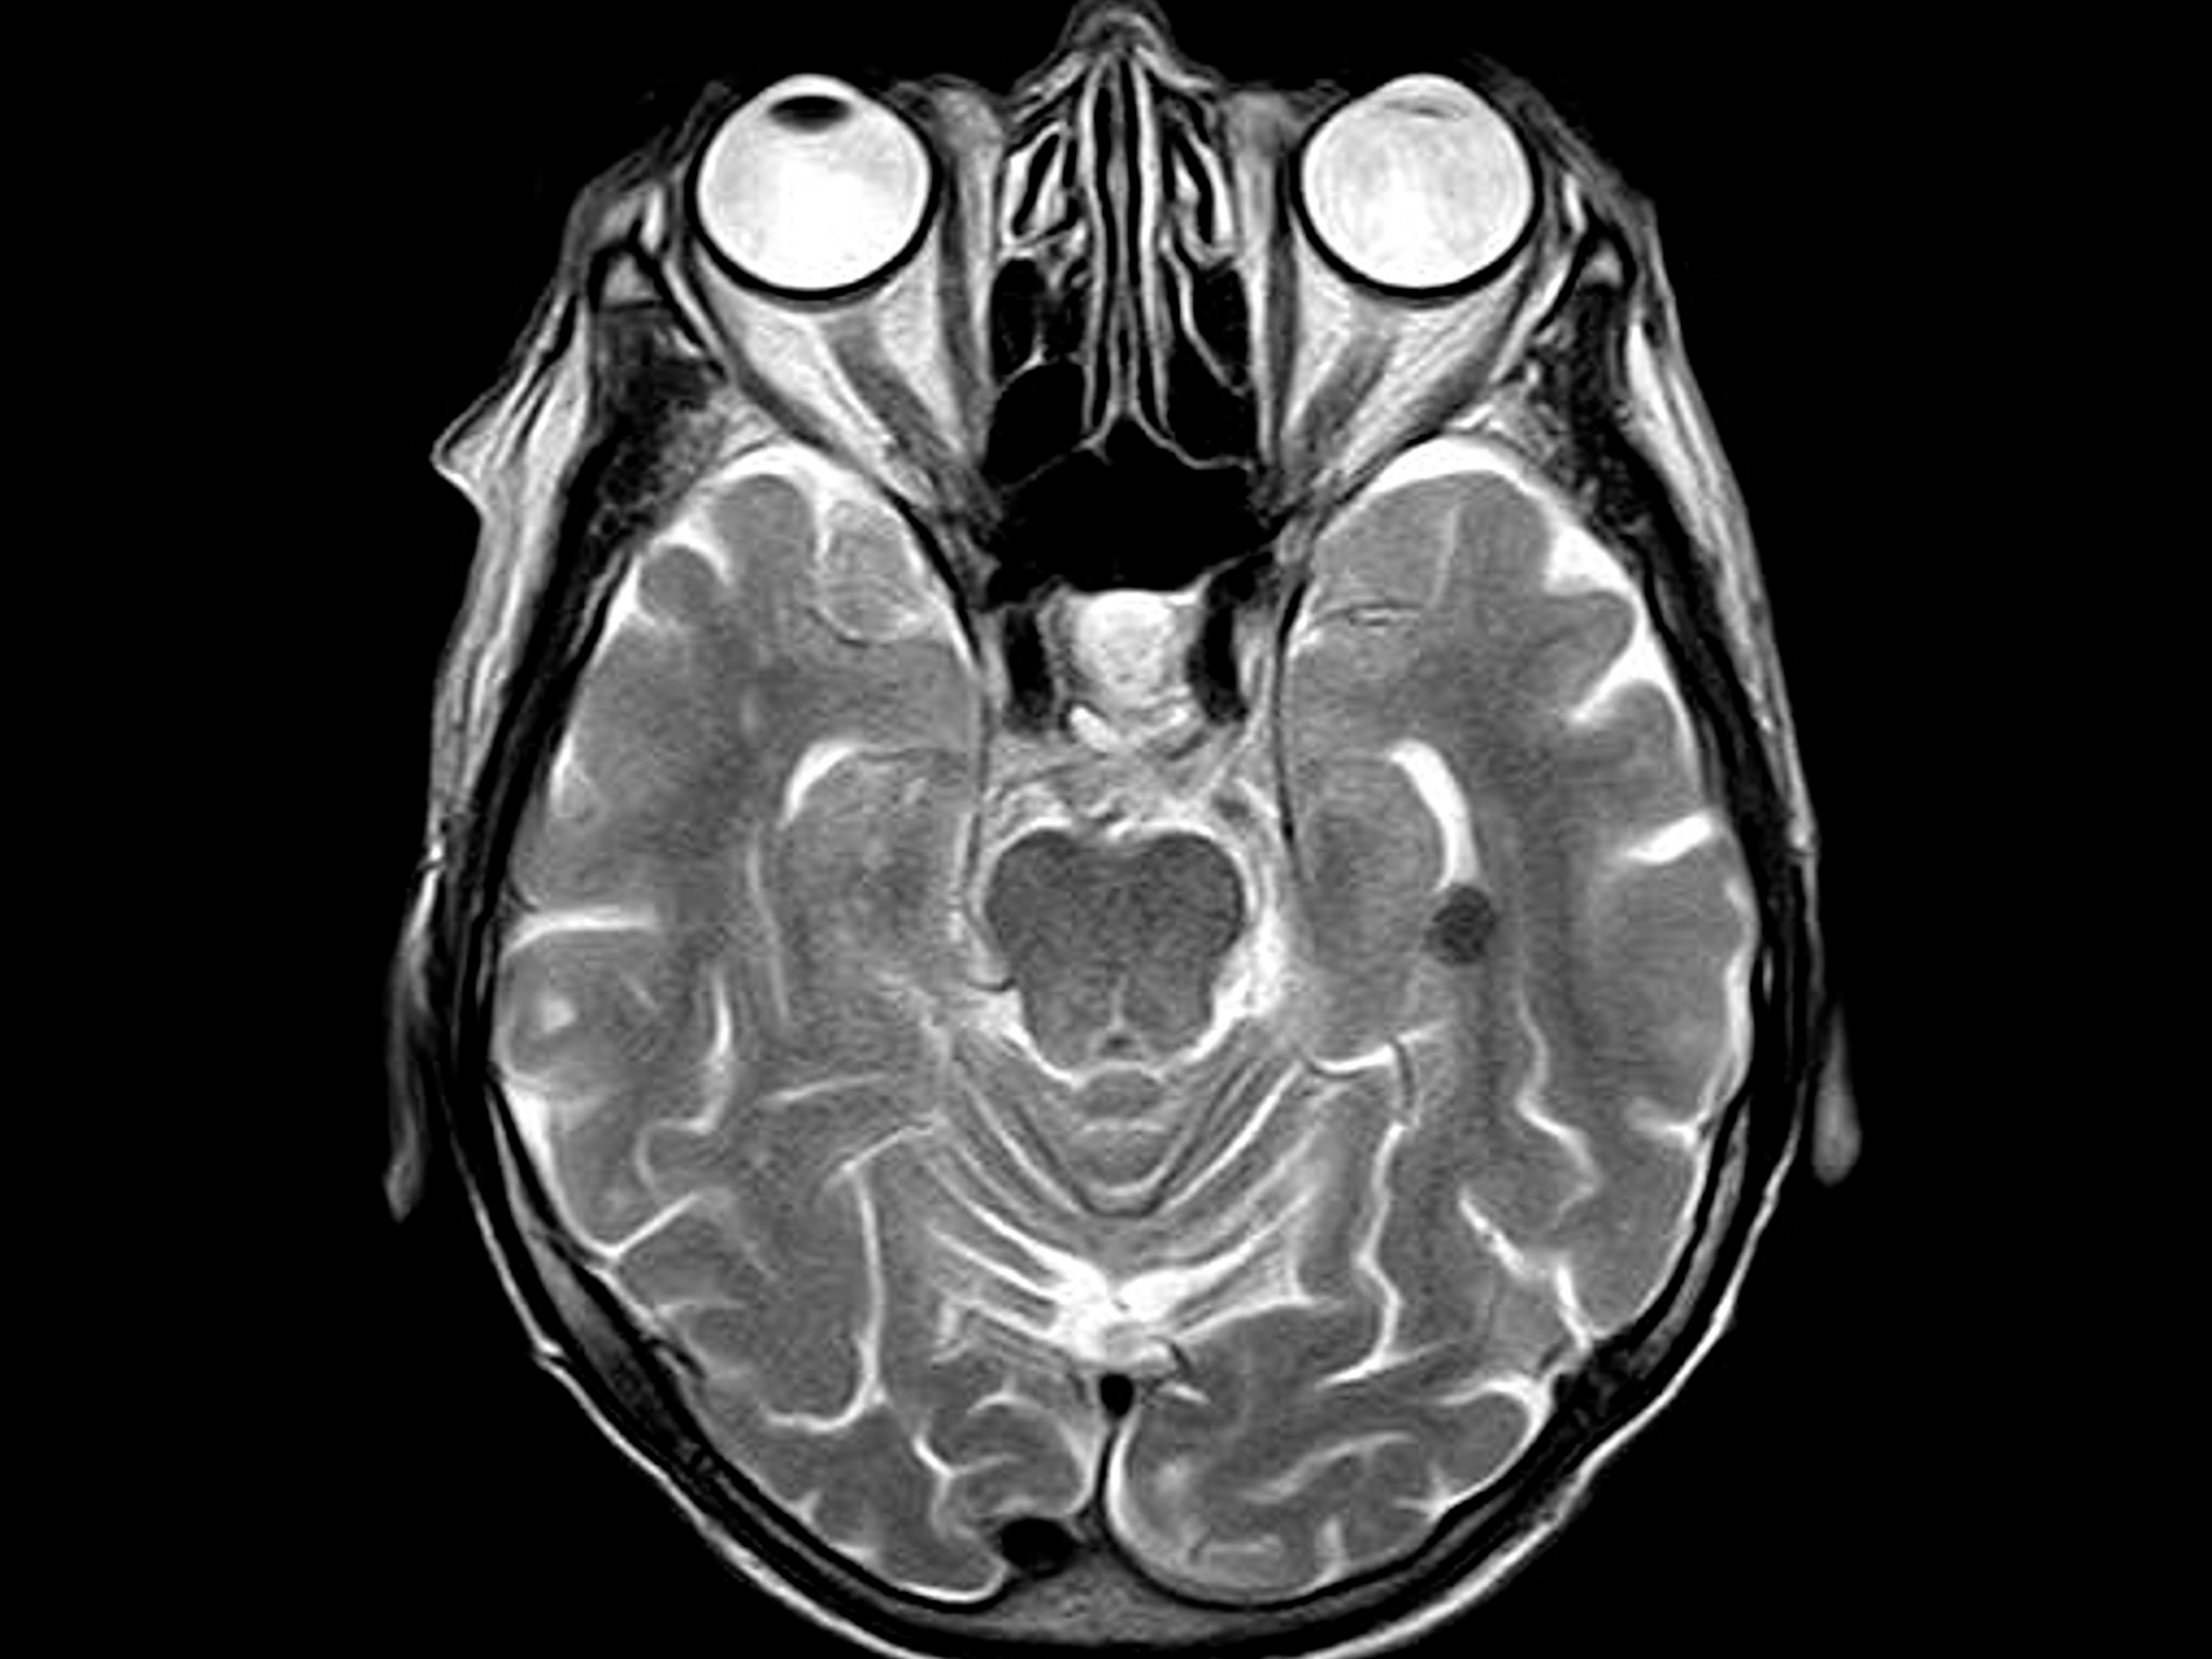

Die oben genannte Patientin hat deutliche Beschwerden in sitzender Position und im Stehen. Eine Untersuchung in einem normalen MRT, die ausschließlich im Liegen stattfindet, ergab bisher keine Erklärung der klinischen Beschwerden der Patientin, ebenso wenig facharztspezifische Untersuchungen. Zusammen mit der Anamnese, die über die Lebensjahre der Patientin viele Kopfverletzungen beinhaltet, deutet dies auf ein funktionelles Problem im Bereich der Kopfgelenke hin, was wiederum mit der komplexen Hirnnervensymptomatik vereinbar ist. Ebenso die deutliche Hypermobilität im Bereich der Halswirbelsäule grenzen die Ursache auf eine funktionelle Dysbalance ein.

Funktionelle Unstimmigkeiten im Bereich der Wirbelsäule, wie Wirbelgleiten, Nervenwurzelirritationen und Spinalkanalstenosen, lassen sich mit einem konventionellen MRT im Liegen nicht darstellen. Ein Upright-MRT, das im Sitzen oder Stehen durchgeführt wird, zeigt anatomische Strukturen unter natürlicher Belastung und unter forcierter Beanspruchung der zu untersuchenden Gelenke.